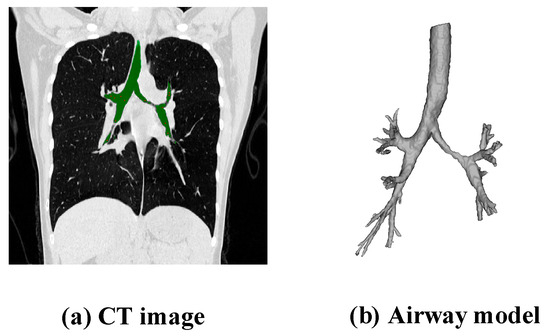

As shown in Figure 2, Figure 2a depicts the patient’s CT image, and Figure 2b shows a schematic diagram of the 3D model of the airway data.

Figure 2.

CT image and 3D model of the airway.